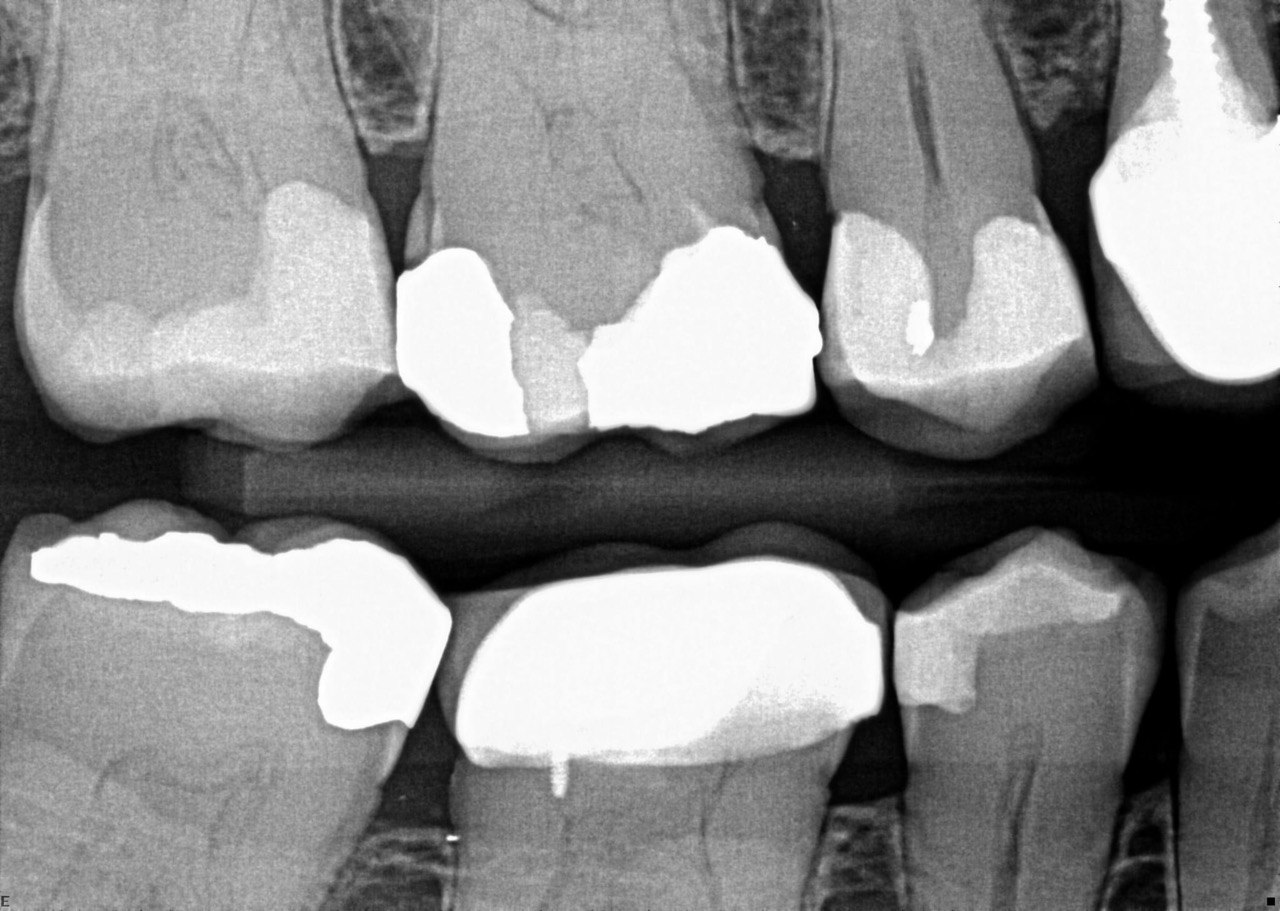

31. What option cannot be selected for the tooth # 3.6?

32. What options cannot be seen in the print of this X ray?

33. What options cannot be seen in the print of this X ray?

34. What option can be selected for tooth # 4.6?

35. What options cannot be selected for the tooth # 1.5?

36. What options cannot be selected for the tooth # 3.7?

37. What options can be selected for tooth # 1.2?

38. What option can be seen in the print of this X ray?

39. What options can be selected for the print of this X ray?

40. What cannot be seen in the print of this X ray?

41. What options cannot be selected for the print of this X ray?

42. What options can be detected for this X ray?

43. What can be selected for the print of the X ray?

44. What option cannot be seen in this X ray?

45. What options are incorrect regarding this X ray?

46. What options cannot be seen in the print of this X ray?

47. What option can be selected for the following X ray?

48. What options cannot be seen in the print of the X ray?

49. What option cannot be selected for the print of this X ray?

50. What option can be selected for this X ray?